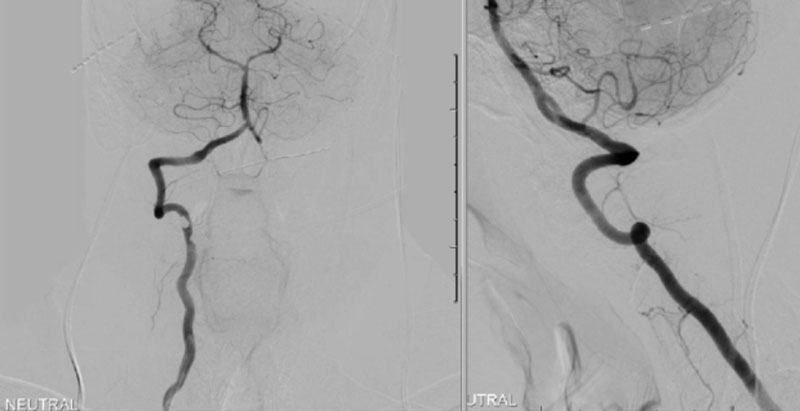

Intraoperative angiography was then repeated again, showing good flow through the right Vertebral Artery into the Basilar Artery. Intraoperative fluoroscopy was then also performed to confirm good position of the screws and rods in both AP and lateral projections. (Figure 7)